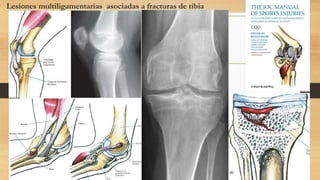

Lesiones multiligamentarias asociadas a fracturas de tibia

Las fracturas de la meseta tibial

medial se asocian con desgarros

del PLC. Las fracturas de la

meseta tibial lateral se asocian con

desgarros de MCL

Las fracturas dela meseta tibial medial se asocian con desgarros del PLC. Las fracturas de la meseta tibial lateral se asocian con desgarros de MCL